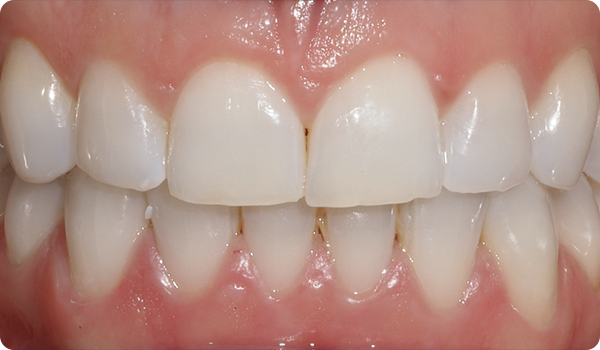

Het uitlijnen van de tanden met Right is de perfecte en meest conservatieve basis voor toekomstige whitening of fineerbehandelingen die de glimlach van de patiënt perfect maken.